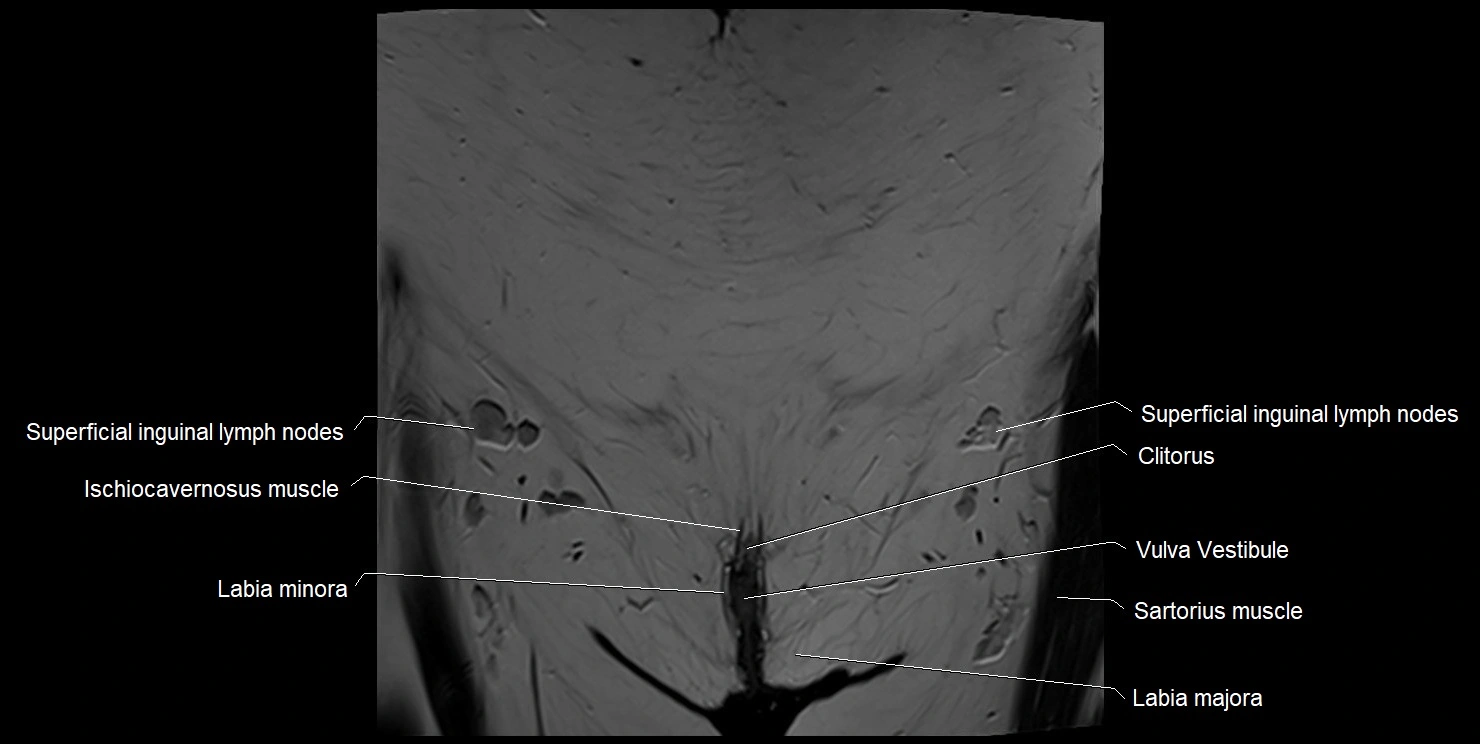

- Clitoris

- Labia majora

- Labia minora

- Superficial inguinal lymph nodes